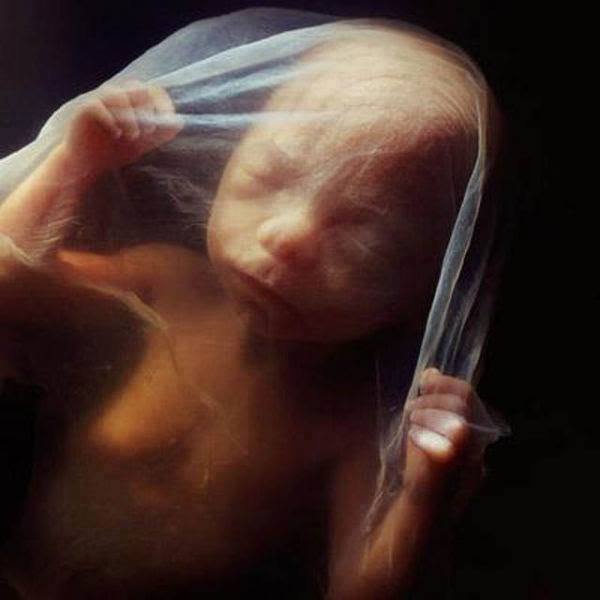

Sarà dopo 8 settimane che il feto comincerà ad assumere una forma umana riconoscibile. Pian piano iniziano poi a formarsi gli occhi, le palpebre, i vasi sanguigni e la cartilagine. Già dopo 16 settimane, il bambino inizierà ad esplorare ciò che lo circonda.

Dopo la ventesima settimana inizia ad apparire una leggera peluria. Al sesto mese il bambino inizia a muoversi, girarsi e a mettersi nella posizione giusta per venire al mondo.